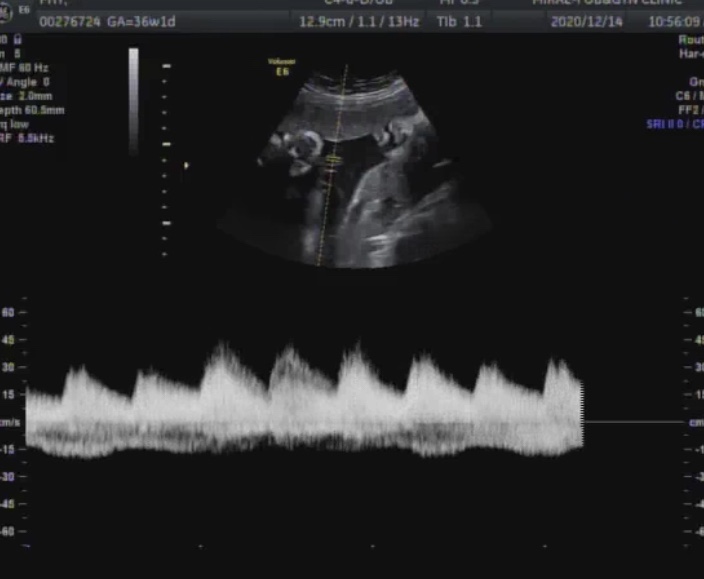

임신37주 태동검사 - 임신후기 증상 - 막달 입덧 - 임신소양증 - 임신성 코피 - 탯줄 감은 태아

#임신후기증상 #막달입덧 #임신소양증 #임신성코피 #임산부코피 #임신37주 #태동검사 #탯줄감은태아 오늘부...